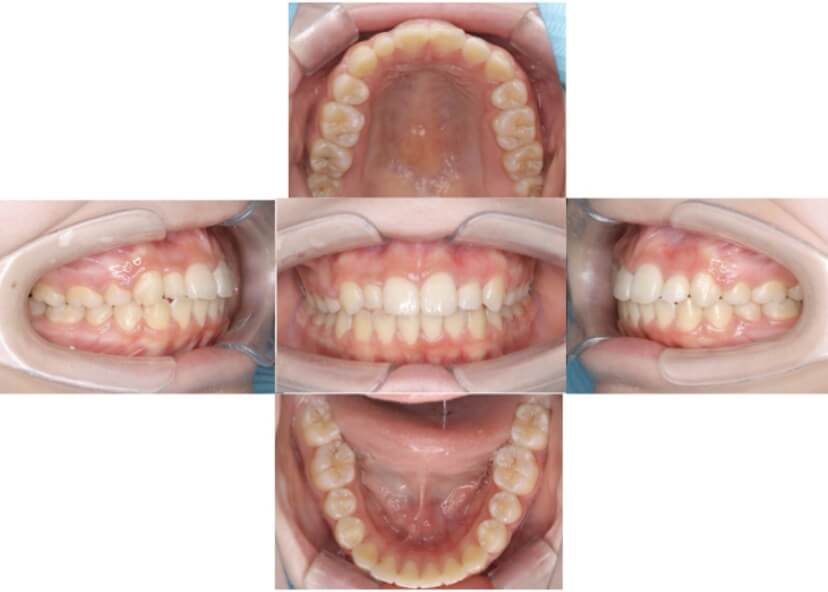

BEFORE

AFTER

上下顎前突、叢生(上下出っ歯、上下の前歯のガタガタ)のケースです。

装置はラビアル(上下表側)で、上下顎の小臼歯を4本抜歯を行っています。抜歯したスペースを使って、上下の前歯の後方移動と叢生(ガタガタ)の改善を行っています。

主訴 前歯のガタガタと口元がでているのが気になる。

年齢・性別 30歳 女性

お住まいの地域 東京都大田区

治療方針 抜歯スペースを利用して上前歯の叢生(ガタガタ)と口元突出の改善

抜歯部位 上下顎左右第一小臼歯

使用装置 ラビアル(上下表側)、顎間ゴム

治療期間 1年11か月

治療回数 13回

リテーナー クリアリテーナー